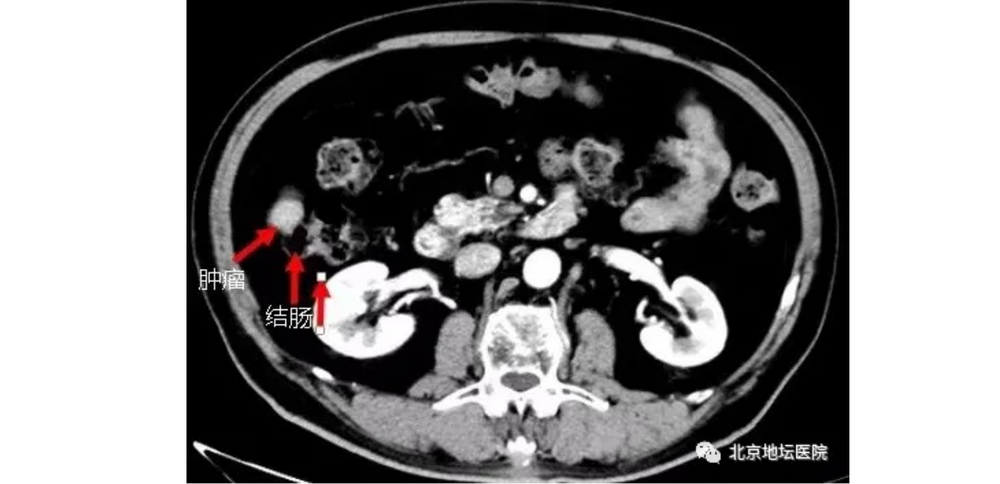

其实,王大爷这个手术的难度相当大。因为肝癌肿瘤病灶位置十分特殊,位于肝脏右后叶边缘,与升结肠紧紧贴在一起,这通常是消融手术的禁区。因为消融产生的热量很有可能把肠子“烫”穿孔,这也是几家三甲医院都建议王大爷保守治疗的原因。

所以,孙巍在进行消融手术前,还进行了一步对手术十分关键的操作——局部水隔离!